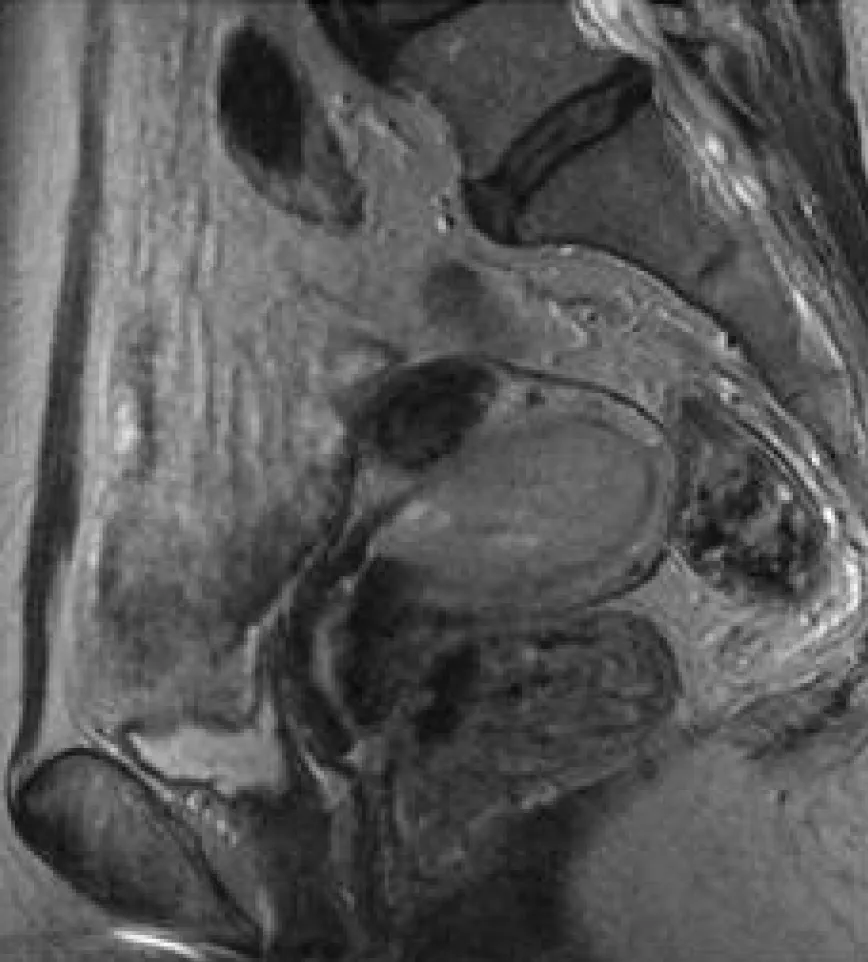

詳解

破題關鍵

這題的解題核心在於辨識子宮頸的解剖位置,並判斷箭頭所指的病灶在T2加權磁振造影(T2WI)上的訊號特徵,來區分常見的婦科腫瘤。圖片中箭頭明確指向子宮頸區域一個訊號偏亮的腫塊,這與子宮頸腫瘤的影像表現高度吻合。

選項拆解

登入查看完整詳解與互動作答